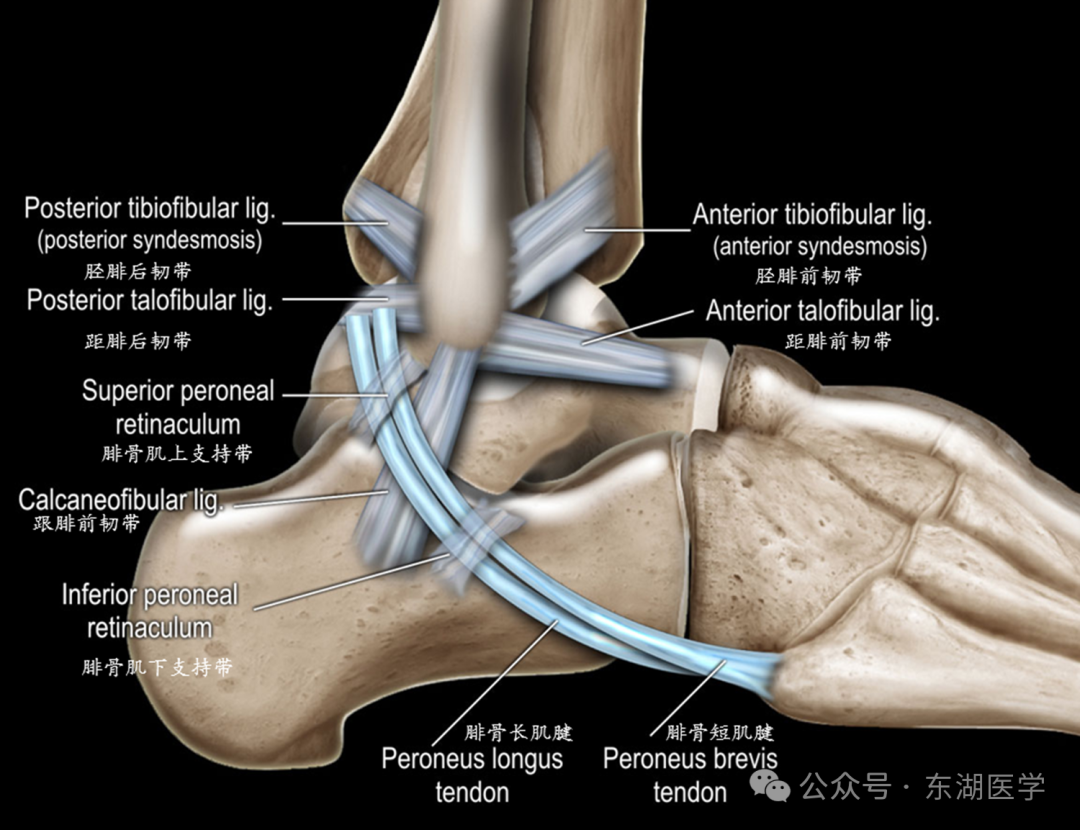

足以骨骼为支架,包括7块跗骨、5块跖骨、14块趾骨,彼此间借关节和韧带相连接。